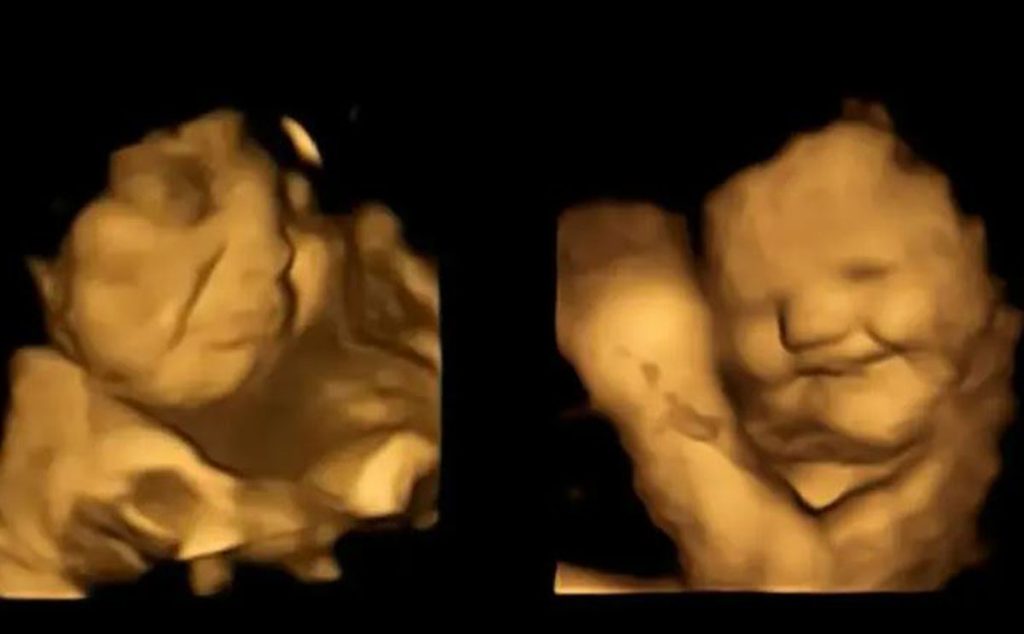

أعطى الباحثون كبسولات تحتوي إما على الجزر أو مسحوق اللفت للنساء الحوامل في الأسبوعين 32 و 36 من الحمل. كشفت عمليات المسح التي أجريت بعد فترة وجيزة من الابتلاع أن الأجنة كانت أكثر عرضة لتكوين “وجوه ضاحكة” عند تعرضها لمذاق الجزر و “وجوه البكاء” بعد مواجهة ملذات اللفت.

في التفاصيل، كتب مؤلفو الدراسة: “يحدث هذا التأثير خلال فترة زمنية قصيرة نسبيًا، أي بعد حوالي 30 دقيقة من تناول الأم لكبسولات النكهة، اكتشفنا تفاعلات وجهية ملحوظة في الأجنة”.